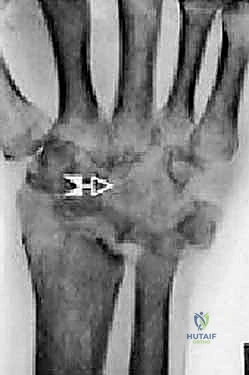

Imaging studies are critical for both diagnosis and templating. Standard posteroanterior (PA), lateral, and oblique wrist radiographs provide sufficient imaging for the vast majority of preoperative planning. In cases of severe deformity, prior trauma, or suspected massive bone loss, a non-contrast computed tomography (CT) scan with 3D reconstructions is highly recommended to assess the precise geometry of the distal radius and the integrity of the capitate and metacarpal bases. Digital or acetate templating is utilized to determine the appropriate size for the radial body and stem, the capitate stem, the carpal plate and body, the scaphoid augment (if utilized), and the lengths of the radial and ulnar fixation screws.

Following capitate reaming, the chosen carpal plate and stem are assembled and inserted into the capitate and seated onto the resected carpal surface. The carpal plate is anchored to the carpus with a radial screw that optimally does not penetrate the second metacarpal, and a second screw placed ulnarly into the hamate. This construct ensures stable distal fixation while avoiding the deleterious lever arm of a long metacarpal stem. Trial reductions are performed to assess stability, range of motion, and impingement. Once kinematics are confirmed, the definitive ultra-high-molecular-weight polyethylene (UHMWPE) body—which is direct compression molded onto a cobalt chrome alloy radial body—is impacted. The capsule and extensor retinaculum are meticulously repaired to prevent extensor tendon bowstringing and provide a robust soft tissue envelope over the implant.